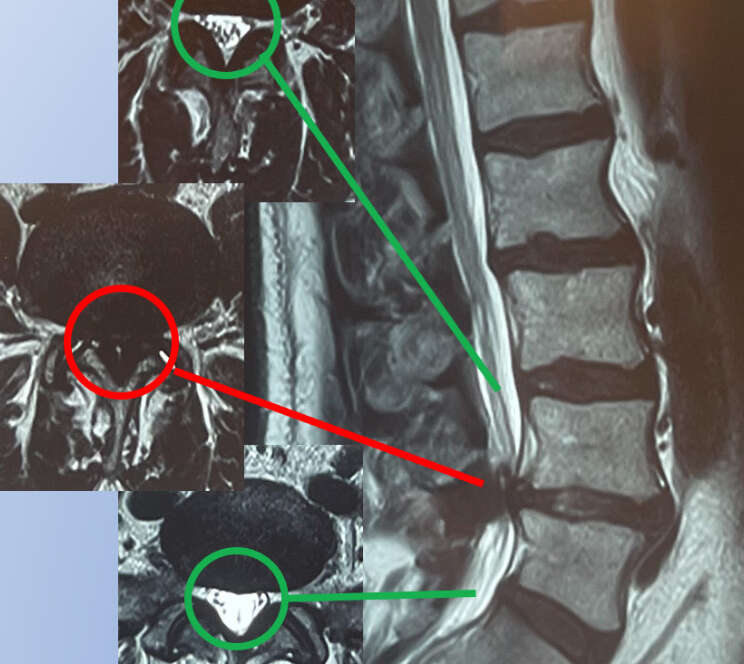

Após uma busca por um médico especialista em coluna, a paciente realizou um agendamento no consultório. Durante a consulta, foi realizada uma anamnese detalhada, explorando minuciosamente as características da dor. O exame físico revelou, na pele da paciente, a presença de múltiplas lesões típicas de Herpes Zoster.

Herpes Zoster é uma infecção viral causada pela reativação do vírus varicela-zoster, o mesmo que causa a catapora. É mais comum em pessoas idosas ou imunossuprimidas. A condição frequentemente se manifesta como uma erupção cutânea dolorosa que segue o trajeto de um nervo, podendo ser confundida com dores de origem na coluna vertebral, como em casos de radiculopatia.

O Herpes Zoster deve ser considerado um diagnóstico diferencial importante em pacientes com dor torácica ou lombar, especialmente quando essa dor é acompanhada de hipersensibilidade ou alterações cutâneas. A identificação precoce do Herpes Zoster é essencial para iniciar o tratamento antiviral adequado, o que pode reduzir a duração e a severidade dos sintomas, além de prevenir complicações, como a neuralgia pós-herpética.